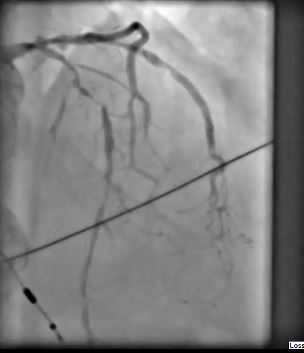

Coronary angiogram: Critical stenosis of the LAD. Severe 3-vessel disease